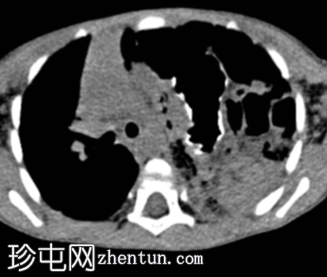

CT

轴向

非造影

左侧膈疝通过位于左膈中部的一个缺损形成,伴有纵隔向右侧移位,下方左塌陷。

脾脏、大肠和小肠均有疝气,同时伴有肠系膜上血管疝气。

胃位于下部,靠近主动脉分叉处。

在降结肠和直肠中可见先前荧光透视检查的残留造影剂。